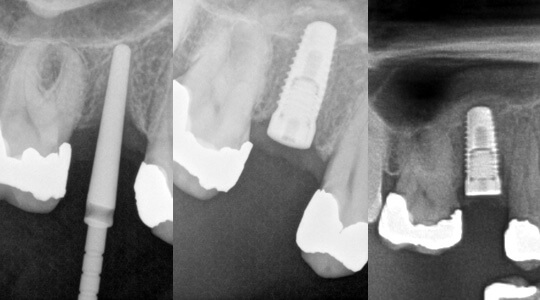

Unzureichende Knochenhöhe bei Implantation eines kleinen oberen Backenzahnes. Einbringen eines Markierungspfostens zur Lagebestimmung.

Durchführung eines minimalinvasiven internen Sinuslift und zeitgleiche Insertion eines Zahnimplantates. Der Boden der Kieferhöhle wurde wie auf dem Röntgenbild erkennbar nach oben angehoben, damit das Implantat auch im oberen Bereich knöchern einwachsen kann.

Röntgenologische Nachkontrolle nach 4 Monaten. Das Implantat steht optimal im Eigenknochen.